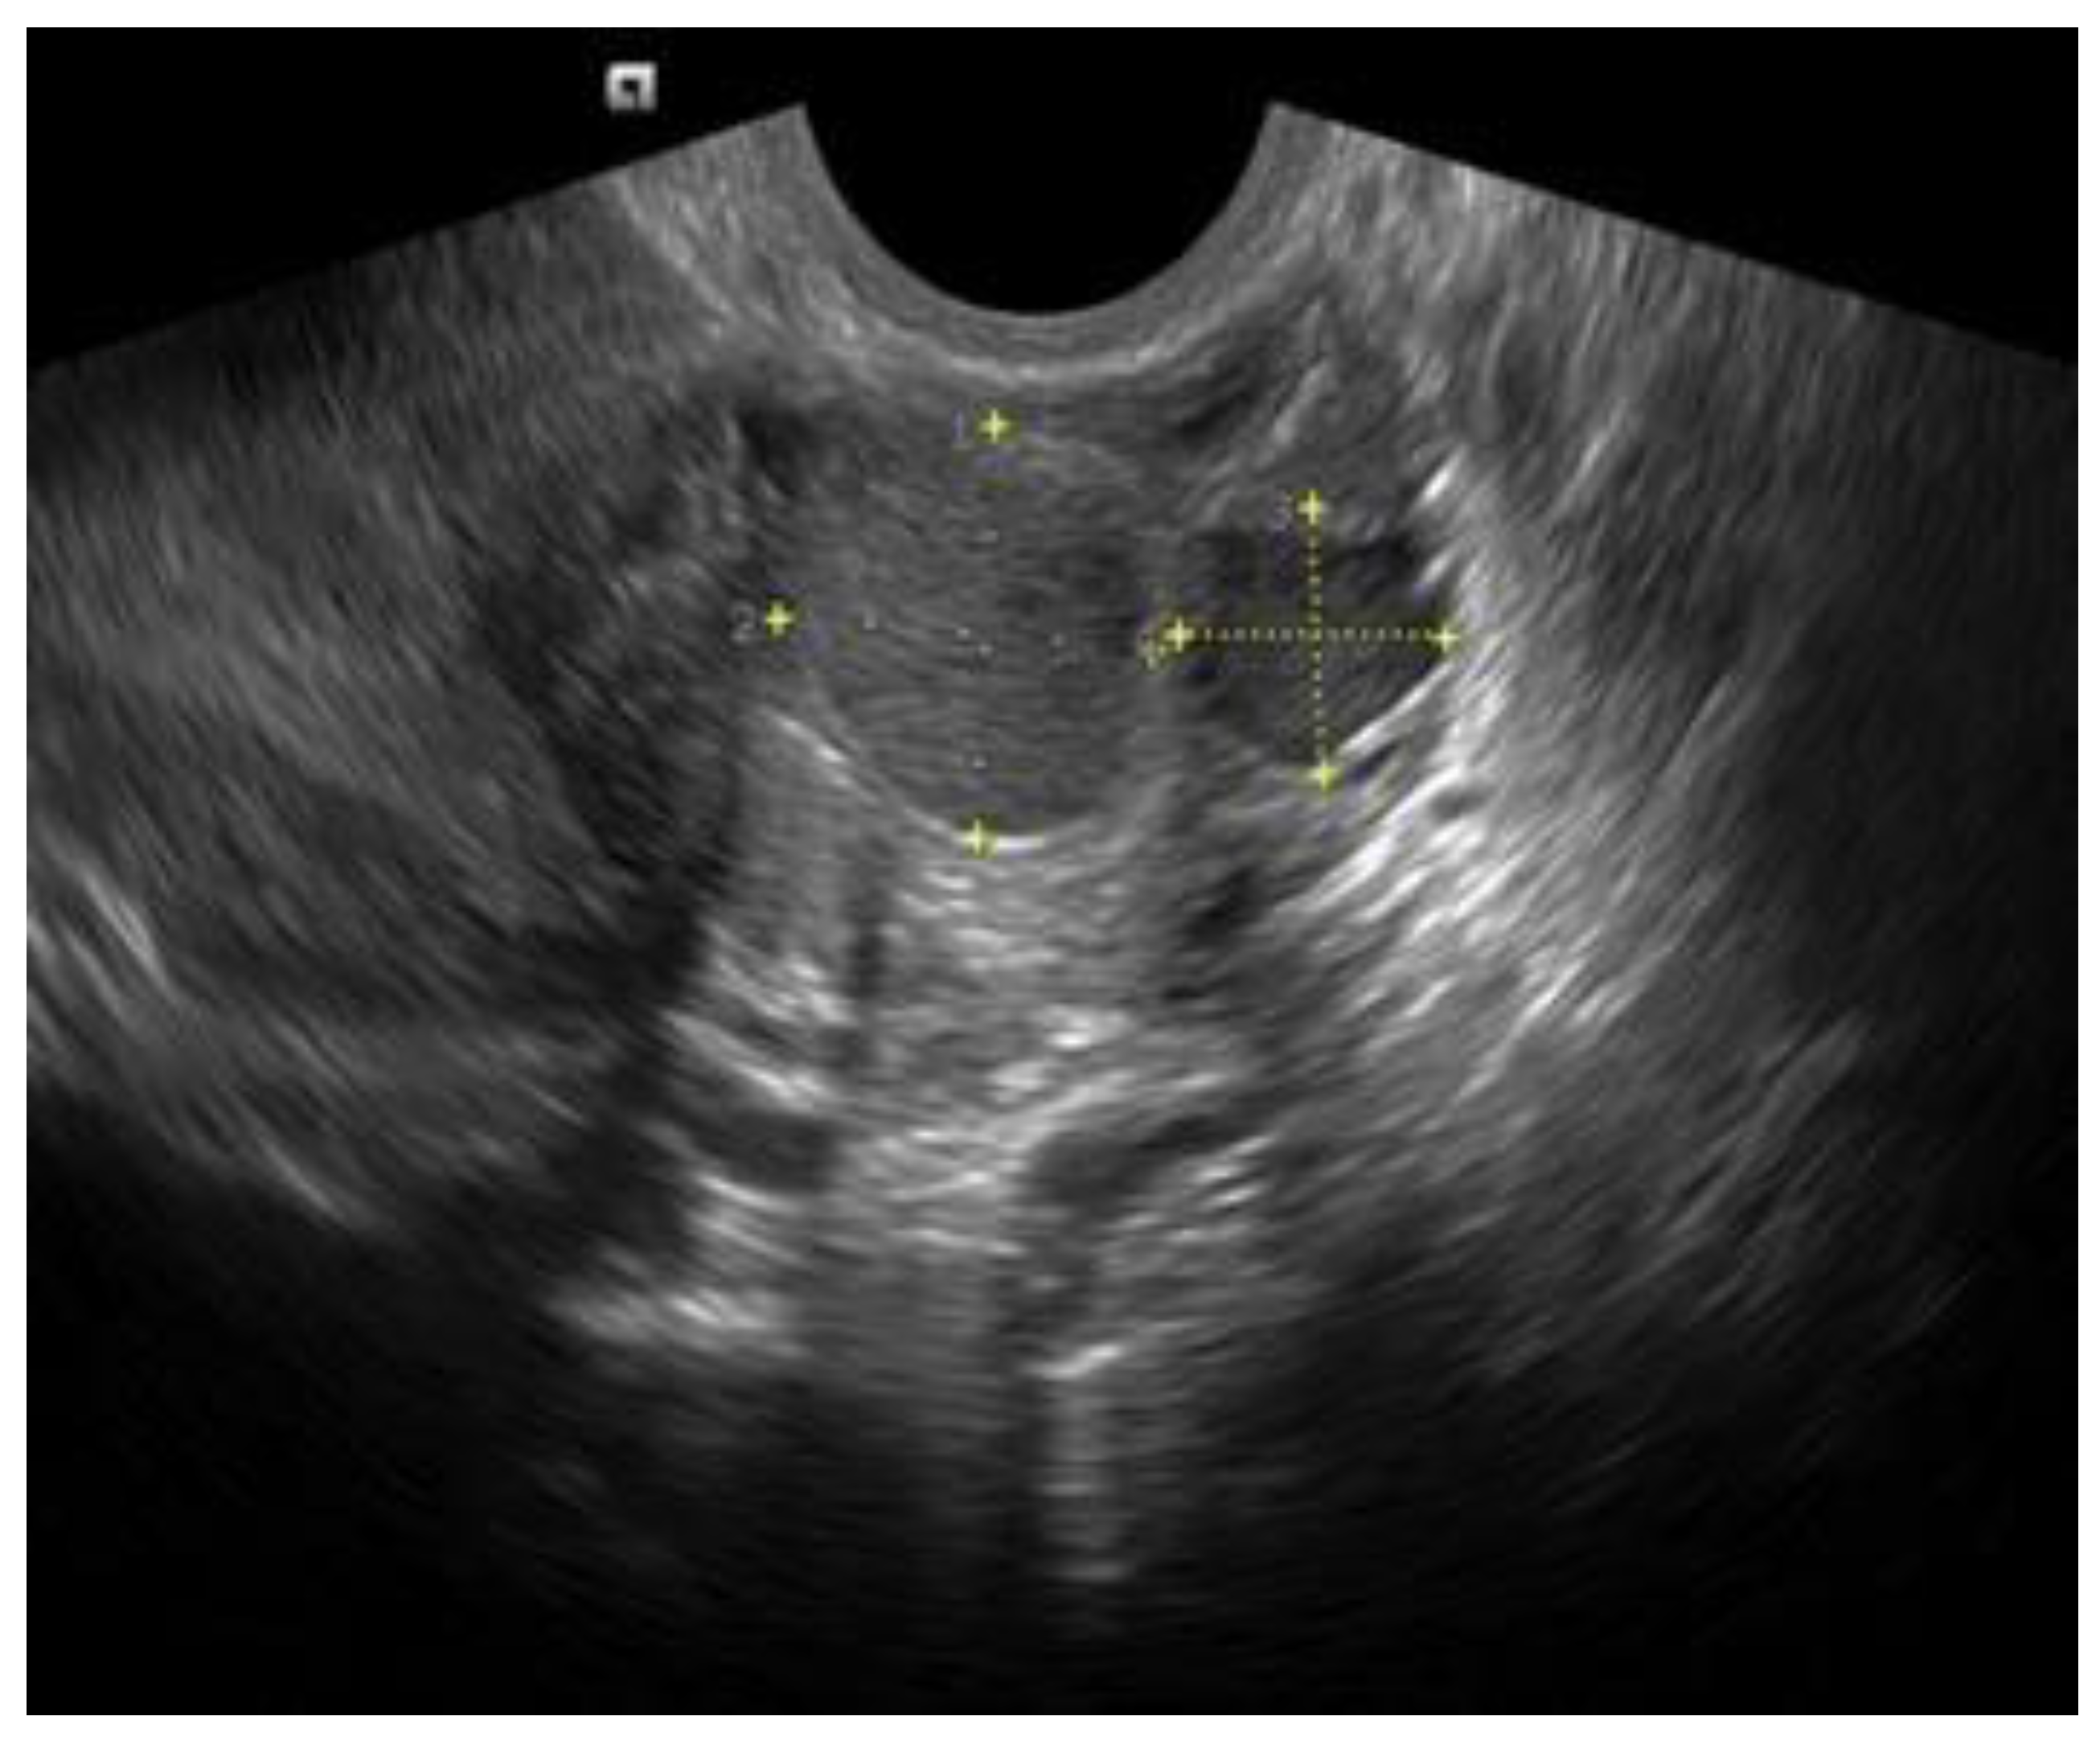

2.1. Ovarian Endometrioma (OΜA)

- Van Holsbeke, C.; Van Calster, B.; Guerriero, S.; Savelli, L.; Paladini, D.; Lissoni, A.A.; Czekierdowski, A.; Fischerová, D.; Zhang, J.; Mestdagh, G.; et al. Endometriomas: Their ultrasound characteristics. Ultrasound Obstet. Gynecol. 2010, 35, 730–740. [Google Scholar] [CrossRef] [PubMed]